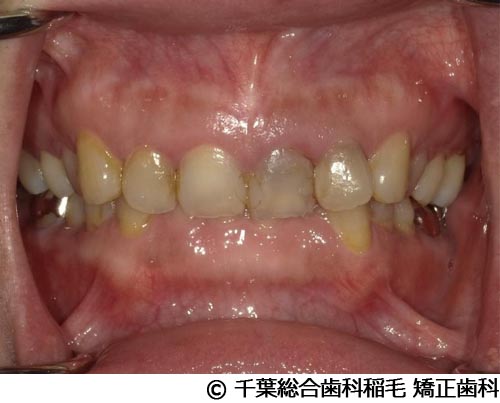

【症例4】上顎前歯1本インプラント埋入手術

- 治療前

- 治療後

- 治療名

- 上顎前歯1本インプラント埋入手術

- 費用

- 600,000円(税込)

- 期間

- 11ヵ月

治療内容

-

患者様の症状

前歯の色味が気になりご来院されました。

治療法

根っこが割れていたため抜歯となりました。

インプラント、ブリッジ、義歯それぞれのメリット、デメリットをお話させていただき、インプラントでの治療を選択されました。 -

治療結果

機能性、審美性ともに改善し、満足していただけました。

現在も定期検診で拝見させていただいています。